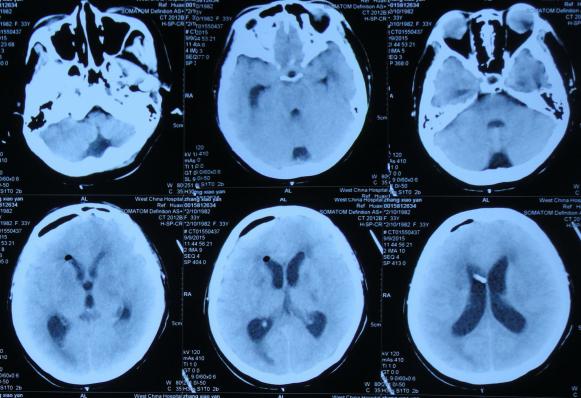

在第1家医院治疗32天后即2015年9月4日,为了进一步的治疗,转入上级的第2家我国西部著名的位于四川省成都市的某三甲医院的神经外科。查头部增强MRI示脑积水,感染性病变可能,结核,脑室系统扩张(图-6);头部CTA示脑积水,双侧基底节区多发低密度影,多系腔梗灶,颅内大血管未见明显异常(图-7);胸部CT:双下肺散在慢性炎症,双侧胸膜增厚,双侧胸腔少量积液(片子丢失)。

图-6:2015年9月4日头部CTA

图-7:2015年9月4日头部MRI增强

第2家医院治疗3天后即2015年9月7日,查头部CT示侧脑室扩张明显(图-8),次日2015年9月8日,进行了右侧侧脑室钻孔外引流术,查脑脊液细菌培养阴性,PPD(结核菌素)试验阴性。

图-8:2015年9月7日头部CT

第2家医院治疗5天后即2015年9月9日(脑室外引流术后2天),查头部CT示脑室稍有缩小(图-9)。

图-9:2015年9月9日头部CT